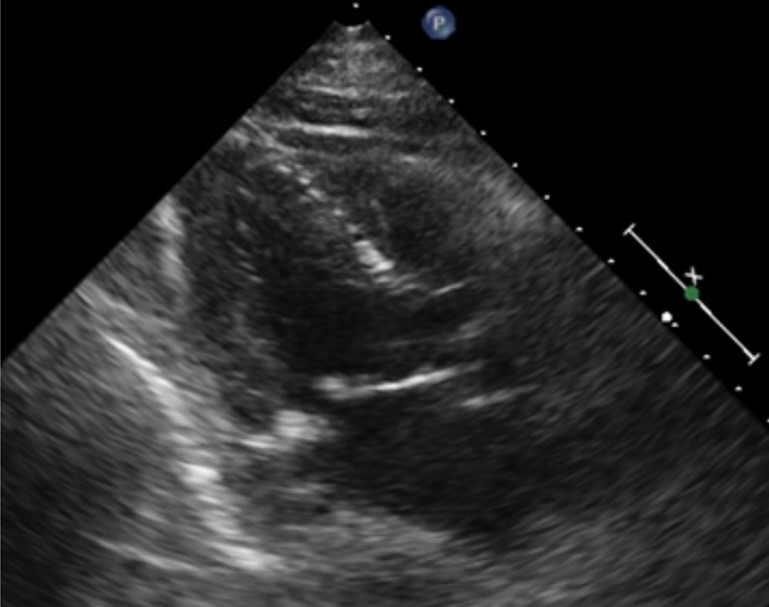

Most Foreshortened Example Least Foreshortened Example

The image on the left illustrates an example of the Most Foreshortened, while the Least Foreshortened example is shown on the right.